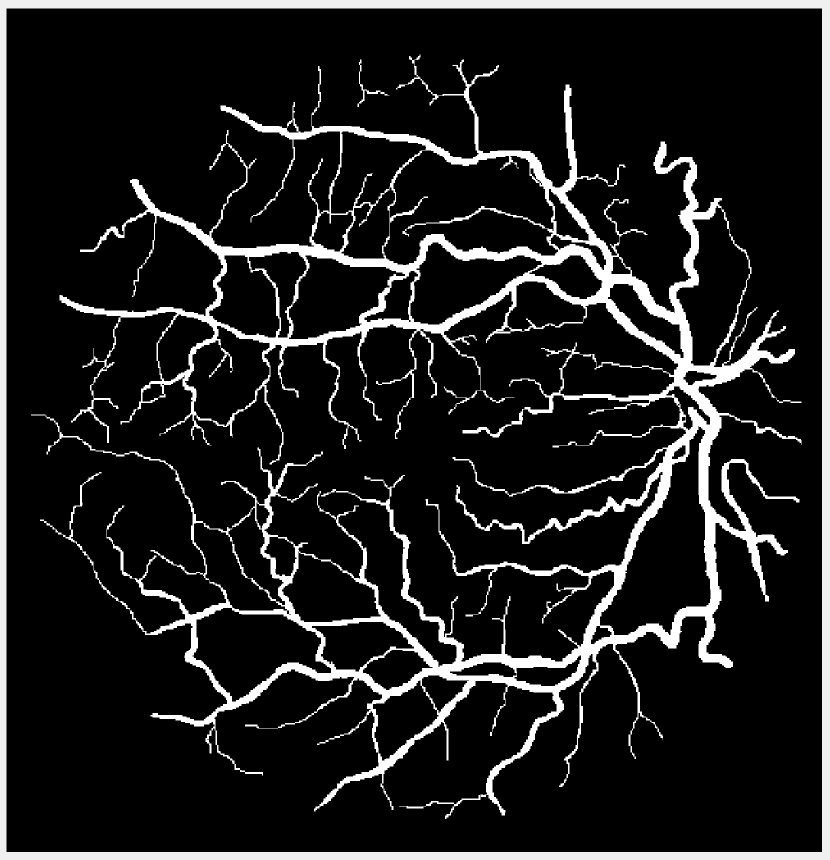

Refer to caption

(a) Vessel 1

Figure 1: Original images for testing. (a)-(c) Retinal vessel images from the DRIVE dataset [23]. Image size is 584×565584565584\times 565 with pixel intensities 191 (vessel) and 104 (background). (d)-(g) Brain images from the BrainWeb dataset [24]. Image size is 104×8710487104\times 87 with pixel intensities 10 (background), 48 (cerebrospinal fluid), 106 (grey matter), and 154 (white matter).

We compare the performance of the proposed TTV-regularized image segmentation model with its counterparts regularized by (isotropic) TV [8], TVp [12], and AITV [15]. The algorithm we use for TV is similar to Algorithm 1 in that we use the 2,1subscript21\ell_{2,1} proximal operator in (7). For TVp, we use the ADMM algorithm following [12] but without the bias term for fair comparison and set p=1/3𝑝13p=1/3 as suggested. For AITV, we use the difference-of-convex algorithm (DCA) [25] designed in [15] and set α=0.5𝛼0.5\alpha=0.5 as suggested. The image segmentation models are applied to the images shown in Figure 1. For Figures 1(a)-1(c), we perform binary segmentation to identify the retina vessels, while for Figures 1(d)-1(g), we perform multiphase segmentation (N=4𝑁4N=4) to identify the cerebrospinal fluid (CSF), grey matter (GM), and white matter (WM) separate from the background. We evaluate the segmentation performance by two metrics: DICE index [26] and Jaccard similarity index [27]. The parameters for each segmentation method are carefully tuned so that we obtain the best DICE indices. Specifically, for Algorithm 1 that solves (4), we set β1=β2=0.25subscript𝛽1subscript𝛽20.25\beta_{1}=\beta_{2}=0.25 and find the optimal parameter λ𝜆\lambda in the range [0.0025,0.05]0.00250.05[0.0025,0.05] for both binary and multiphase segmentation. For binary segmentation, we select the best value for a{5,10,100}𝑎510100a\in\{5,10,100\} while for multiphase segmentation, we select for a{1,5,10}𝑎1510a\in\{1,5,10\}. Algorithm 1 is initialized with the results of fuzzy c𝑐c-means clustering [28] and it terminates either when UtUt1FUtF<104subscriptnormsuperscript𝑈𝑡superscript𝑈𝑡1𝐹subscriptnormsuperscript𝑈𝑡𝐹superscript104\frac{\|U^{t}-U^{t-1}\|_{F}}{\|U^{t}\|_{F}}<10^{-4} or after 200 iterations. The experiments are performed in MATLAB R2022b on a Dell laptop with a 1.80 GHz Intel Core i7-8565U processor and 16.0 GB of RAM. The code for Algorithm 1 is available at https://github.com/JimTheBarbarian/Official-TTV-Segmentation.